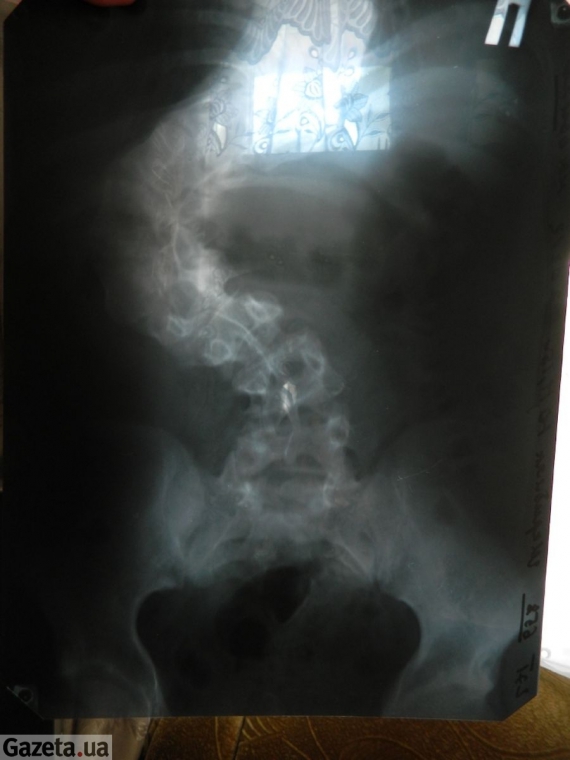

Саме він був лікарем 15-річного Юрка Шкрібляка із Тернопільщини. У цьому інституті у Харкові школяру вирівняли 120-градусне викривлення хребта. Після двох операцій хлопець виріс на 11 см.

"Уже при 40-градусному викривленні хребта людині, незалежно від віку, рекомендовано операцію. І що раніше її провести, то краще для хворого. У Юрка був складний випадок. Викривлення хребта становило 120 градусів", - повідомив він.

ФОТОРЕПОРТАЖ: 15-річному школяреві вирівняли хребет, який мав 120-градусне викривлення